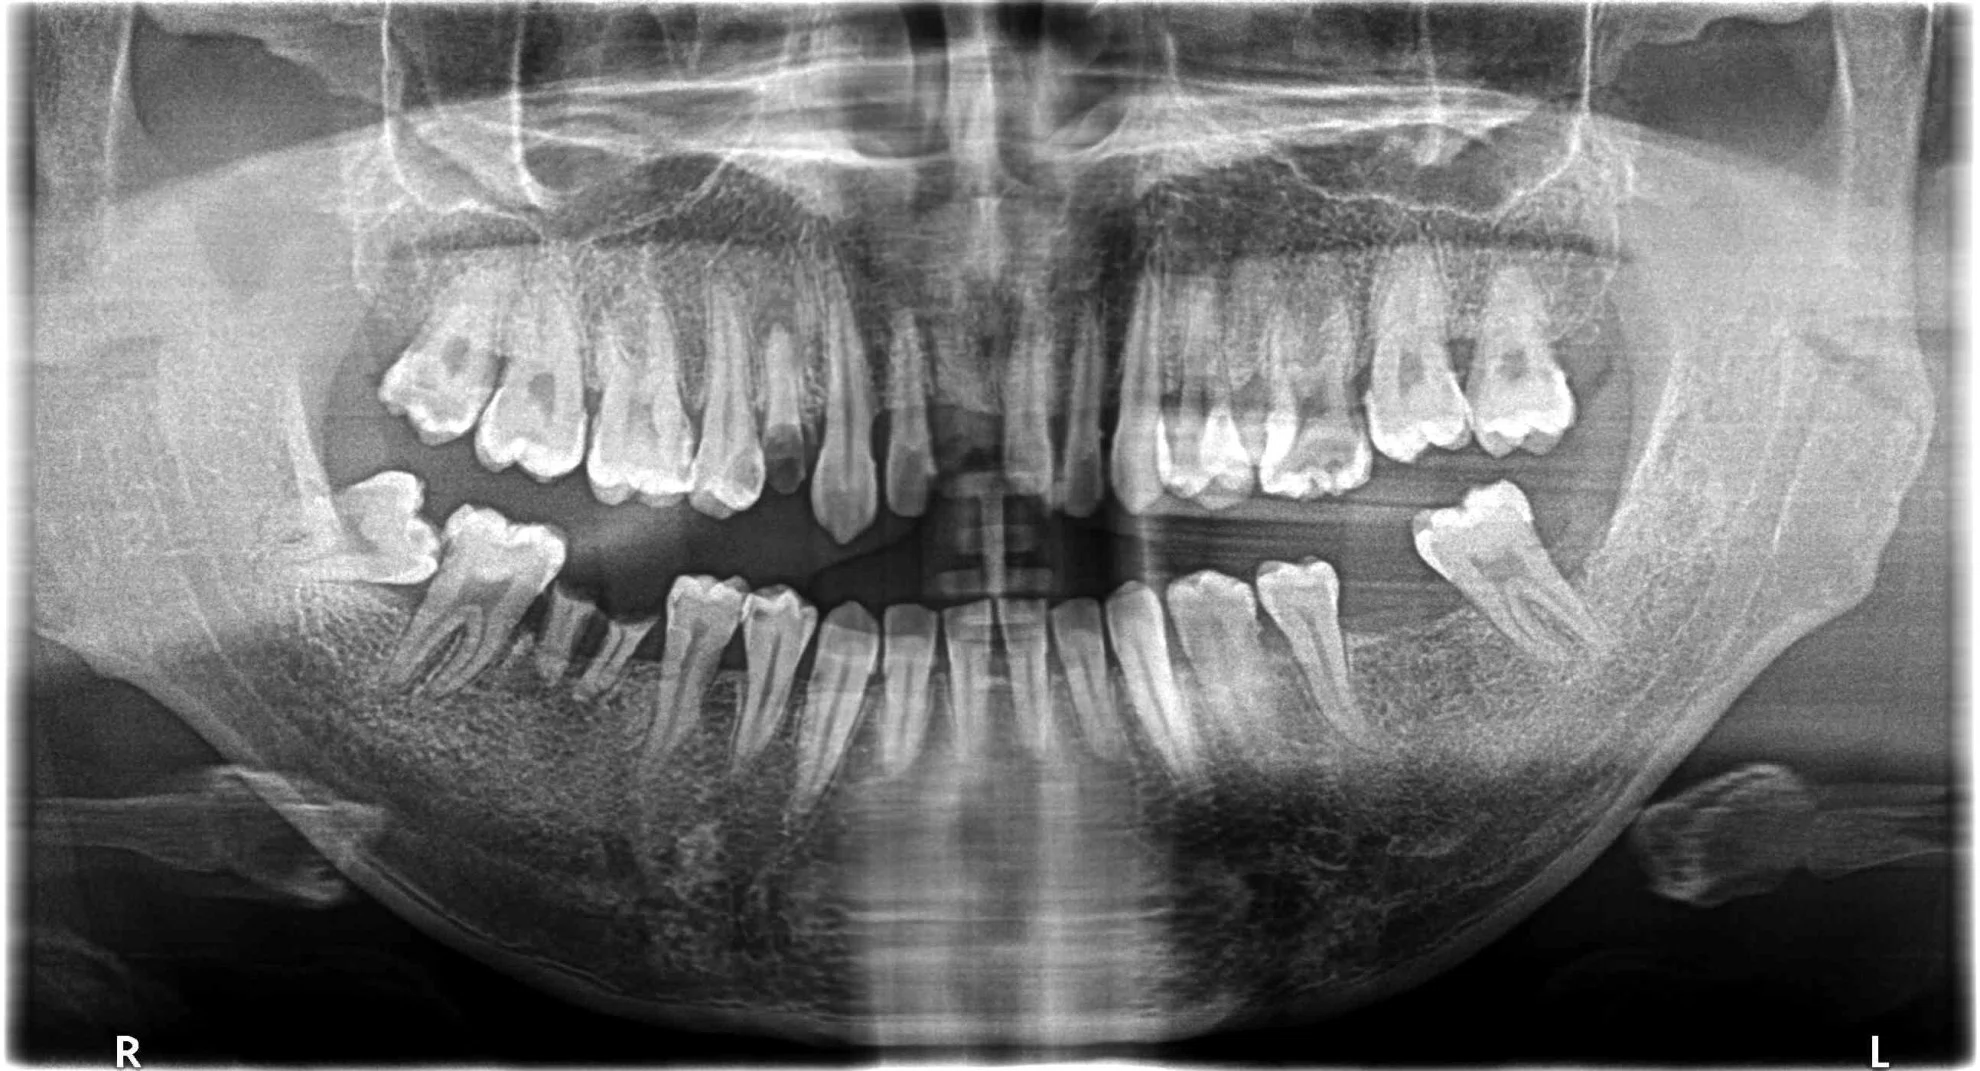

這位患者的治療挑戰涵蓋了缺牙、受損牙齒的修復,以及對最終美觀的極高要求。我們透過一系列數位化、微創化的治療流程,成功重建了患者的口腔健康與自信笑容。

後牙區觀察到多處缺牙,可能伴隨齒槽骨條件的考量。成功植入多顆人工牙根 (植牙),X光片顯示植體位置精準,骨整合情況良好,為恢復咀嚼功能奠定堅實基礎。

前牙區可見多顆牙齒的齒質狀況與根尖健康需要處理。根管治療成功完成,並搭配全瓷冠進行修復,重建了牙齒的形態與強度。